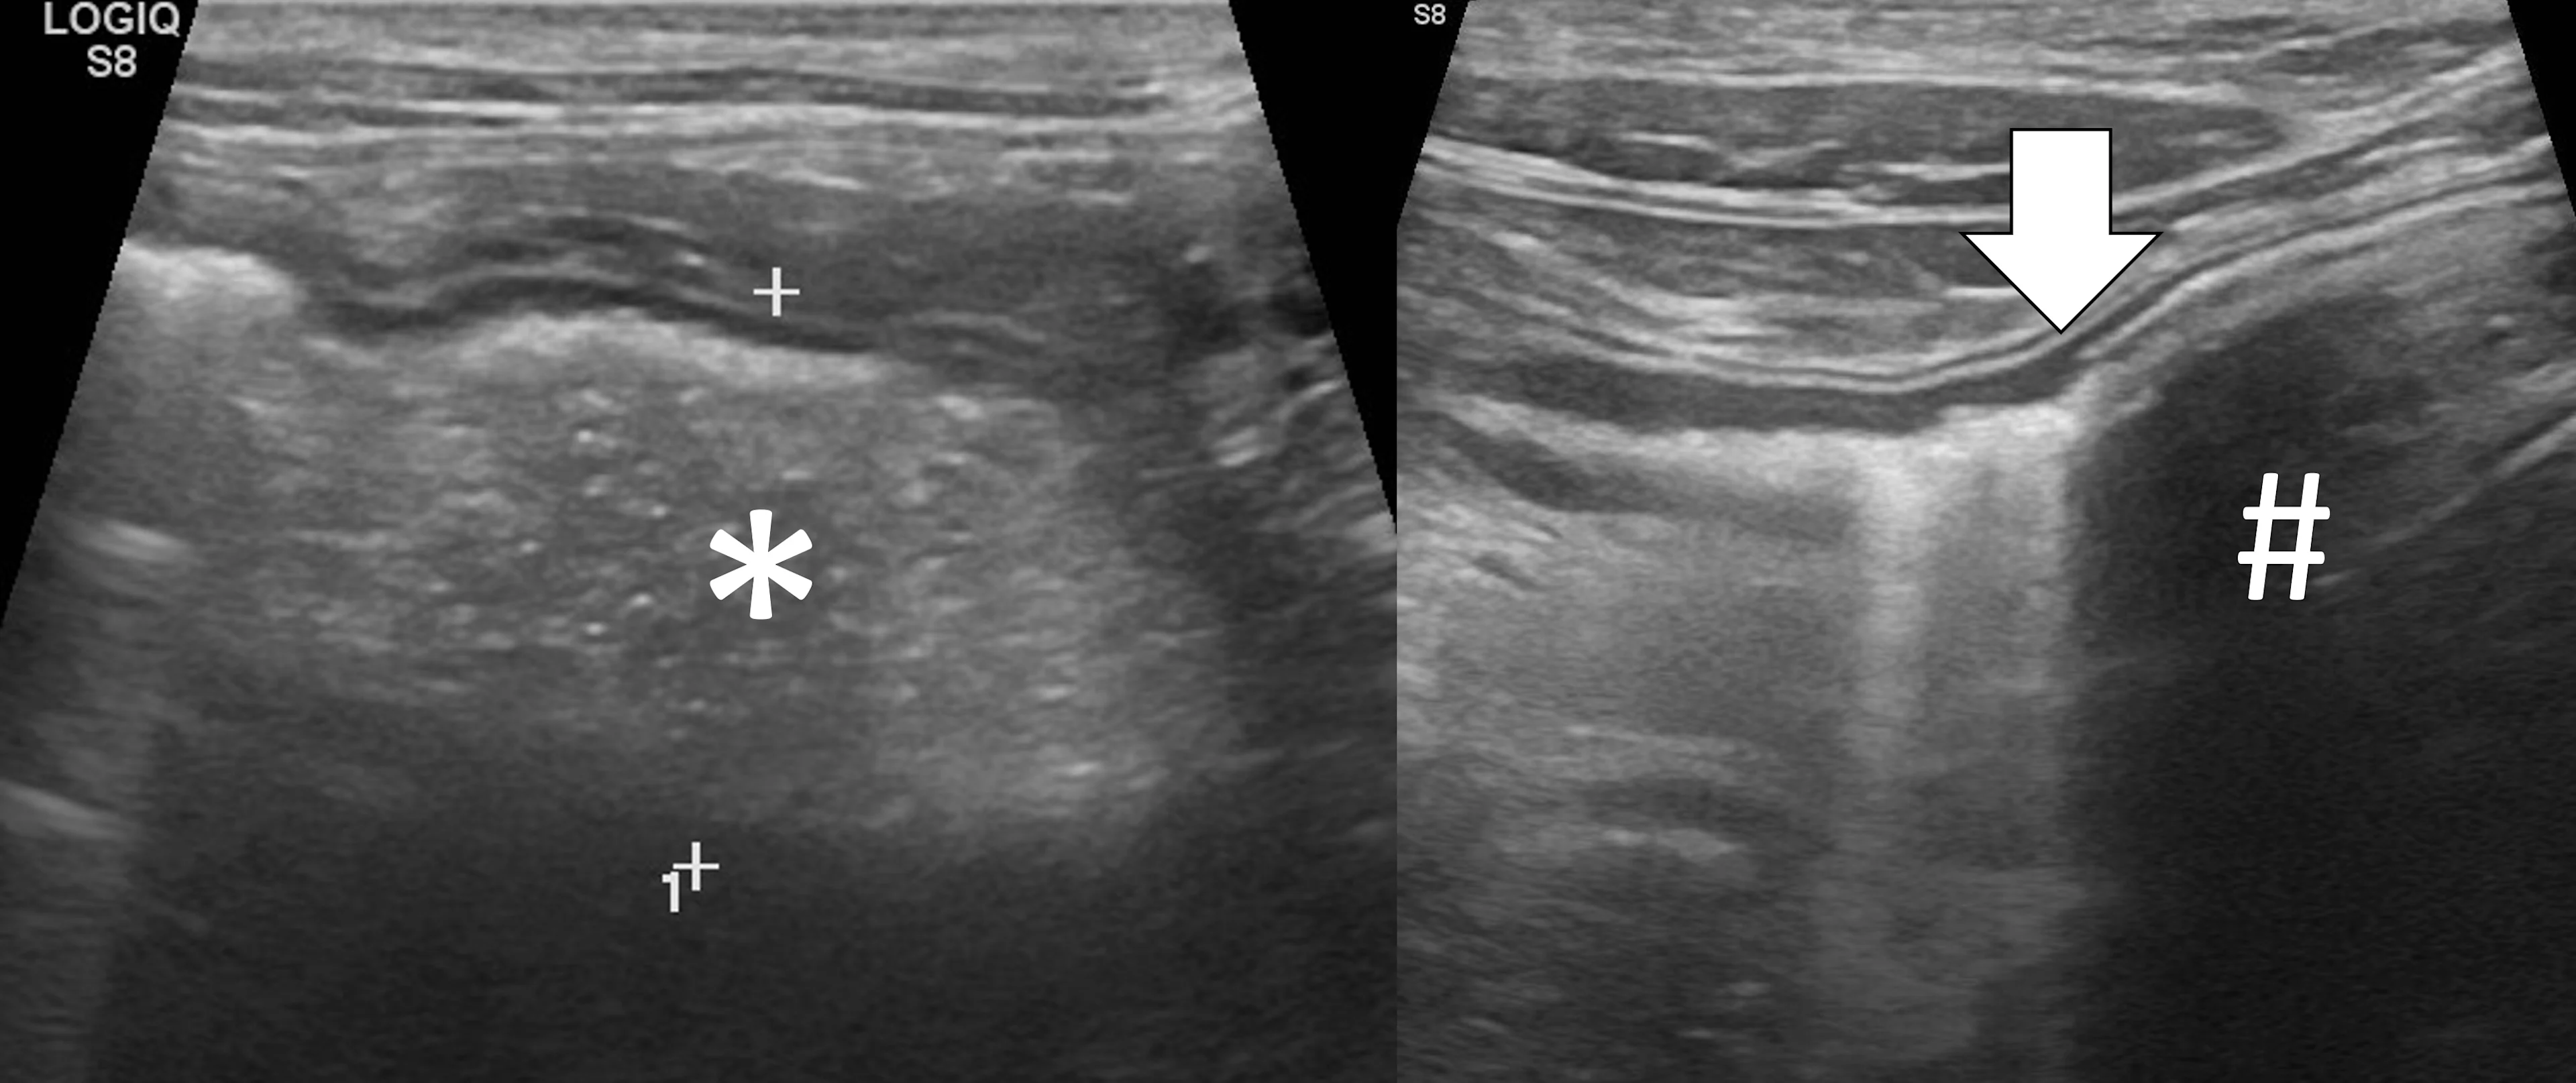

The majority of GI foreign bodies are denser than surrounding soft tissues and fluid. Most of the ultrasonography beam is reflected when there is a sudden change in tissue density (more accurately, acoustic impedance), and further echoes deep to that surface are not produced. The resultant image is a bright hyperechoic line that contours to the shape of the foreign body (eg, plastic toys, rubber balls, cloth, bones, metal), with variable distal acoustic shadowing (Figure 1).9-12 Foreign bodies filled with gas have a similar appearing hyperechoic surface but cause a reverberation artifact (ie, dirty shadow). The entire foreign body will be visible if it is hollow and filled with fluid or has a density similar to soft tissue. Locating foreign bodies can be challenging when only the surface is visualized, but ultrasonography can help detect other changes associated with pyloric outflow, small intestinal mechanical, and linear foreign body obstructions.

Abdominal ultrasound of a 6-year-old neutered male crossbreed dog with a surgically confirmed foreign body (cloth) in the duodenum. The cloth is seen as a hyperechoic curvilinear structure (arrow) that causes a distal acoustic shadow (asterisk).